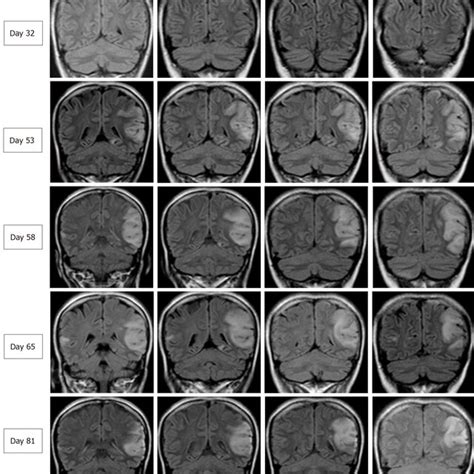

researchgate.net

Serial Brain Magnetic Res…

Serial brain images covering three recur…

320×320